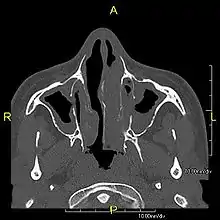

Sagittal CT image showing "tree in bud" appearance of mucous impaction in distal small airways related to primary ciliary dyskinesia

CT image showing dilated and thickened medium-sized airways (bronchiectasis) in a patient with Kartagener syndrome

Oblique sagittal CT image showing lower lobe cylindrical bronchiectasis in the same patient